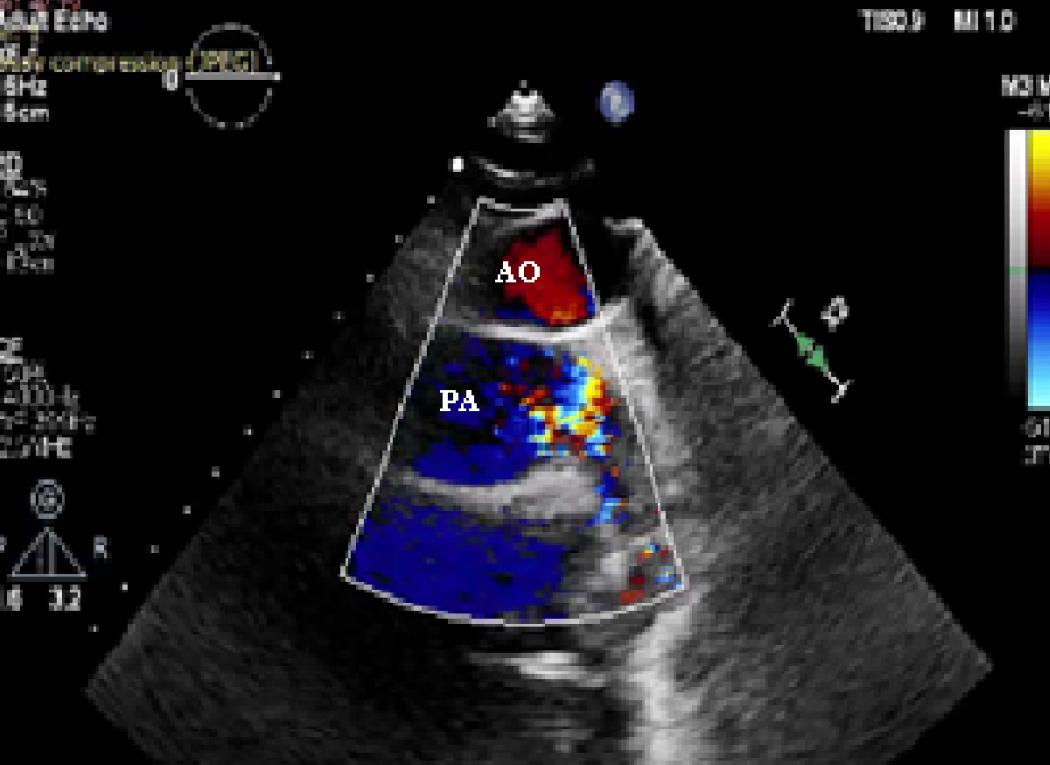

Figure 3